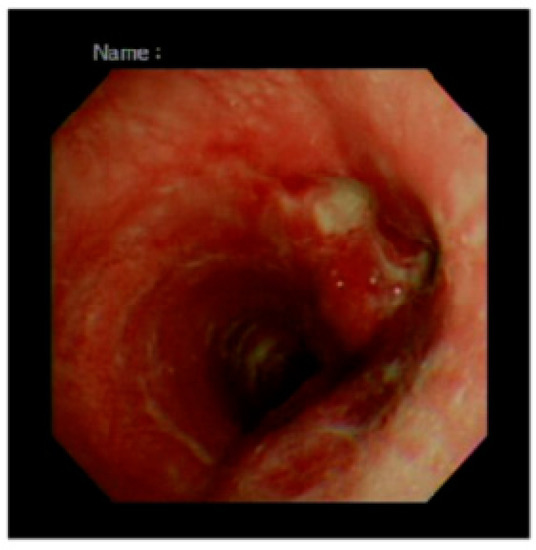

2.1. Case 1